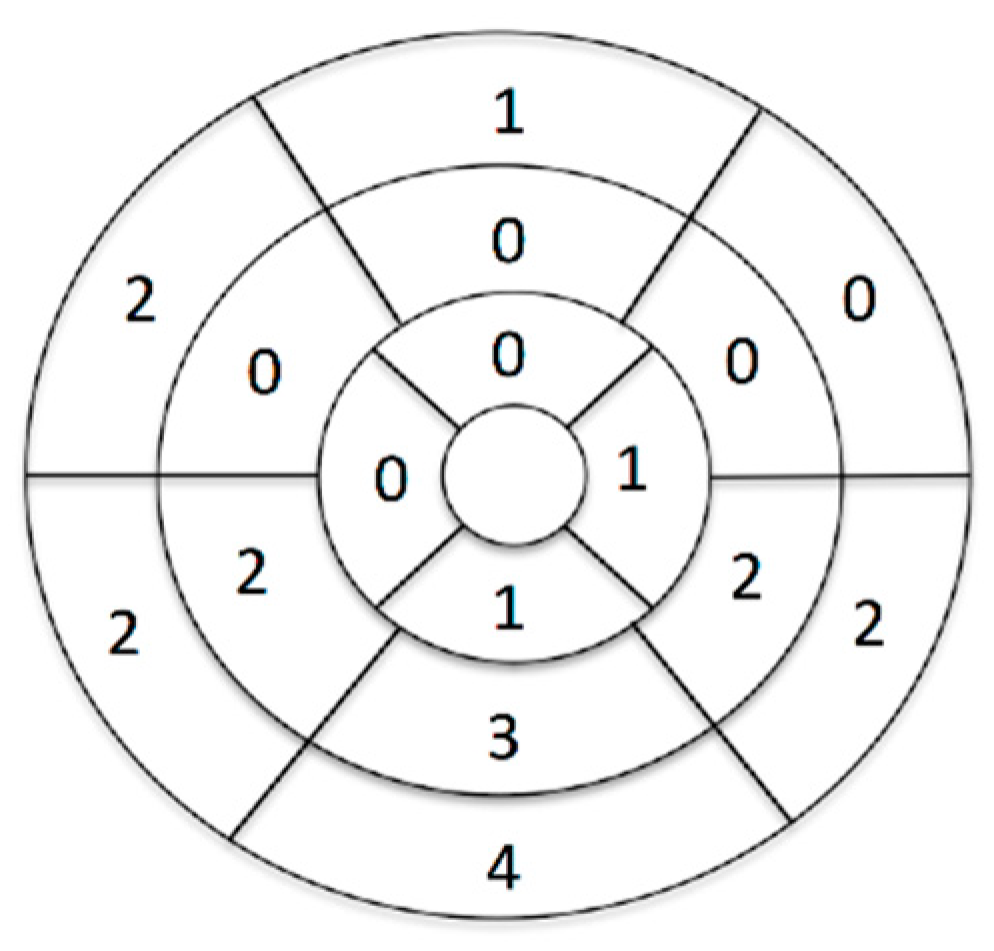

3.2. CMR Findings